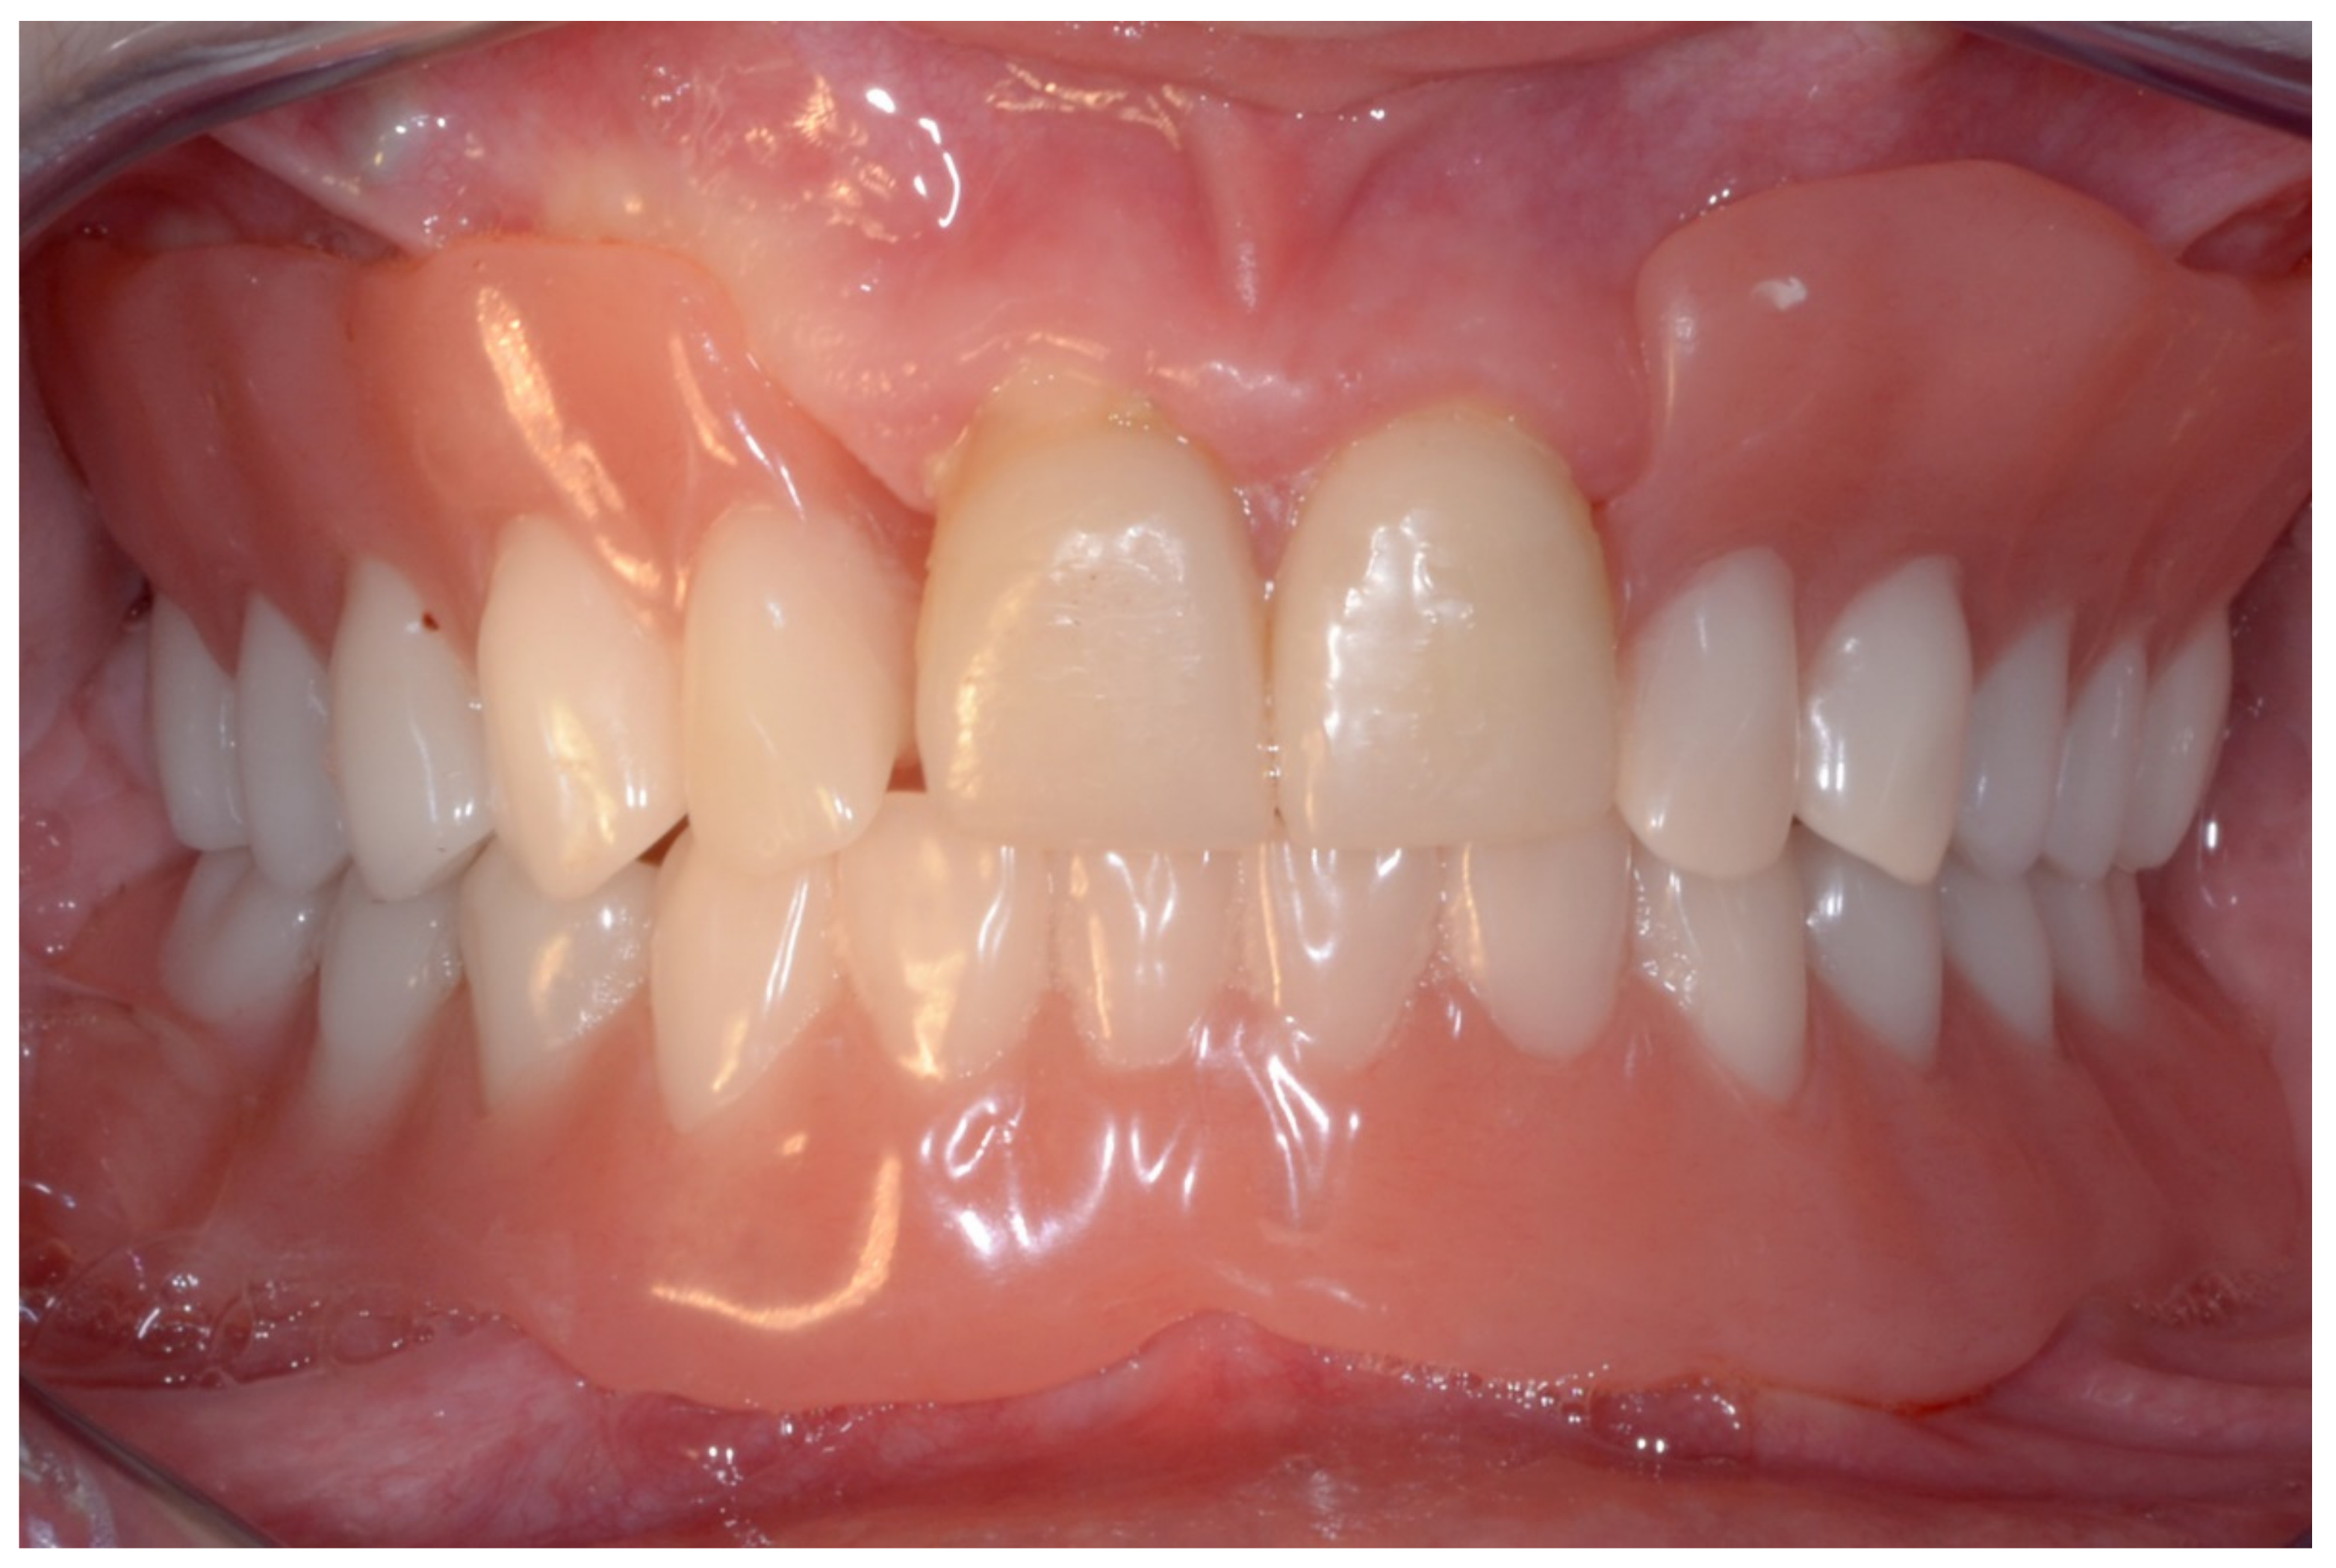

6.1.5. Postoperative (5-Years Follow-Up) Documentation:

A screw-retained provisional fixed prosthesis was used for 4 months to condition peri-implant mucosa, and in January 2019, the final prosthesis was installed. The occlusion was adjusted, and the patient received instruction for oral hygiene. A follow-up assessment at 5 years showed a stable cosmetic, biological and functional reconstruction (Figure 12, Figure 13 and Figure 14).

Figure 12.

Resting frontal close-up views.

Figure 13.

Smile frontal close-up views.